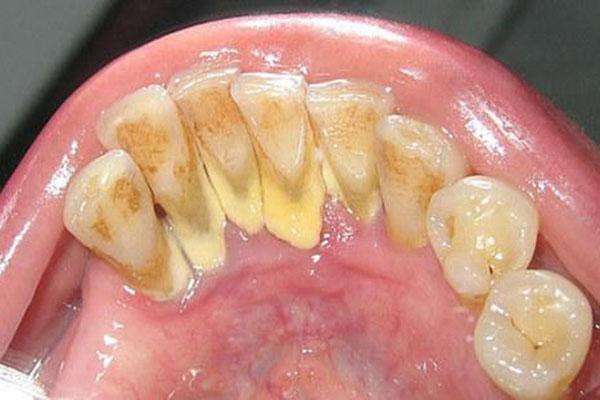

受新冠肺炎疫情的影响,洗牙、刮治等牙周诊疗项目由于喷溅类操作较多,所以很多人可能都经历无法就诊的时候。那在不能洗牙的日子里,有人“想尽方法”去除牙垢;也有人听说“洗牙没有必要”… 今天,就来为大家揭秘牙周健康的几大谣言。 听说:洗牙会让牙齿越来越松,牙缝越来越大? 真相:洗牙洗晚了才会这样 两颗牙之间塞满牙石,像楔子一样把牙齿紧紧挤在一起。所以大量牙石存在时,牙齿不松都是假象,这个假象掩盖了牙石引起骨吸收,最终导致牙齿松动的本质。 为了终止牙周炎的进展,让牙齿不再继续松动下去,必须要把牙石去掉。牙石去掉短期内,牙齿松动会加剧,随着治疗进展、炎症消除,牙齿周围的根基重新坚固,这种松动是会得到改善的。即使真的由于牙槽骨缺损太多,牙齿松动得不到缓解,可以用一些牙科专业材料进行“加固”。 牙周炎导致牙齿松动,牙缝形成。红肿的牙龈和巨大的牙石占据着牙缝,往往让人感觉不到。一旦牙石去掉,患者往往会感觉牙齿漏风。 通过专业的洗牙去除了牙石,牙龈开始消肿,恢复健康状态,患者往往会感觉牙齿之间有缝隙了。其实使用牙线之后有这种感觉也是这个原因,就是牙龈慢慢恢复健康了。 听说:每天认真刷两次牙就不用洗牙了? 真相:洗牙洗掉的是牙石,牙石刷不掉 牙石是唾液中的钙和细菌沉积在牙齿上形成的。口腔中的唾液和细菌都是无穷无尽的,即使是牙医自己,仅靠刷牙,也不能做到把牙齿上的脏东西完全刷掉。 边边角角刷不到的,日积月累,就形成了一块块牙石,像牡蛎趴在海边的石头上一样,牙石就黏在了你的牙齿上,然后慢慢长大,可结实了,刷都刷不掉。这时候就要借助牙医的专业工具,来做一次彻底的大扫除。 听说:洗完牙以后牙齿特别敏感? 真相:越敏感证明你越有可能已经得了牙周病 洗过牙之后,牙齿变得敏感,表示你已经患有或轻或重的牙周炎了。洗牙仅是牙齿敏感的诱因,真正的根源还是牙周病。 而如果因为害怕敏感而不敢、不愿洗牙,那么将会导致牙周病愈演愈烈,最终牙齿松动脱落。如需克服敏感,可以使用抗敏感牙膏减轻不适。 听说:用红糖水刷牙可以去除牙垢? 真相:红糖只会加速牙齿的腐蚀 听说厨房口腔护理达人又“开发”了新的“护牙”窍门,即用红糖水刷牙,还有的加盐加醋加蚝油加蒜泥等。 红糖也是糖,用红糖水来刷牙,相当于给嘴里剩余的细菌提供了大量养分,加快了细菌的增殖,细菌会产生更多的酸性物质,也可能会导致牙齿表面的色素脱落,但那是以牙齿腐蚀为代价的,对口腔健康百害而无一利。经常和红糖一起出现在谣言里的还有醋、各类水果、各类厨房用品,一定不要试图用这种方式来去除牙石。 听说:牙线会让牙缝变大? 真相: 不用牙线才会让牙缝变大的更快 首先,牙线是一种比较特殊的线,一般都是由多根超细纤维组成的,这些纤维在通过牙齿和牙齿之间时会被挤扁、变形,不会人为的把牙缝撑开。 另外,牙线清理的是牙齿之间的细菌和食物残渣,起到的是清洁作用,不是破坏作用。牙齿和牙齿之间本来就是有缝隙的,这个缝隙不是被牙龈填满,就是被食物残渣填满。 所以很多人都在用过牙线之后有一种“通透”的感觉,以至于感觉是牙缝“被增大了”,其实不是,就是牙缝重见光明了。 再有,如果之前有一定的牙周炎症,那么牙缝之间的充满了细菌,牙龈是肿胀的,一旦养成了用牙线的习惯,把牙缝清理干净了,牙龈炎症减轻了,牙龈也就消肿了,那么也会觉得“牙缝变大了”。 口腔问题不容忽视,出现牙龈出血、肿痛、牙痛等症状都要重视起来,及早治疗。此外做好预防和保护是重中之重,首先要做到早晚两次正确刷牙,饭后漱口、使用牙线;注意定期进行口腔检查,一般半年或一年一次,建议大众定期洗牙,必要时接受牙周治疗。